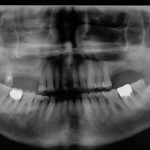

Riabilitazione parziale del mascellare edentulo posteriore con applicazione del principio All-on-4

La riabilitazione dell’edentulia parziale nel mascellare posteriore rappresenta una sfida a causa della densità ossea inferiore e dell’insufficiente quantità di osso dovuta alla presenza...